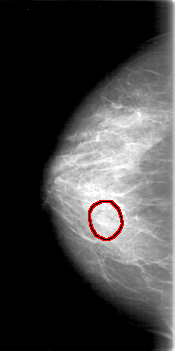

D_4018_1.RIGHT_MLO

RIGHT_MLO LINES 5311 PIXELS_PER_LINE 2671 BITS_PER_PIXEL 12 RESOLUTION 43.5 OVERLAY

FILE: D_4018_1.RIGHT_MLO.OVERLAY

TOTAL_ABNORMALITIES 1

ABNORMALITY 1

LESION_TYPE MASS SHAPE ROUND MARGINS OBSCURED

ASSESSMENT 0

SUBTLETY 4

PATHOLOGY BENIGN

TOTAL_OUTLINES 1

BOUNDARY